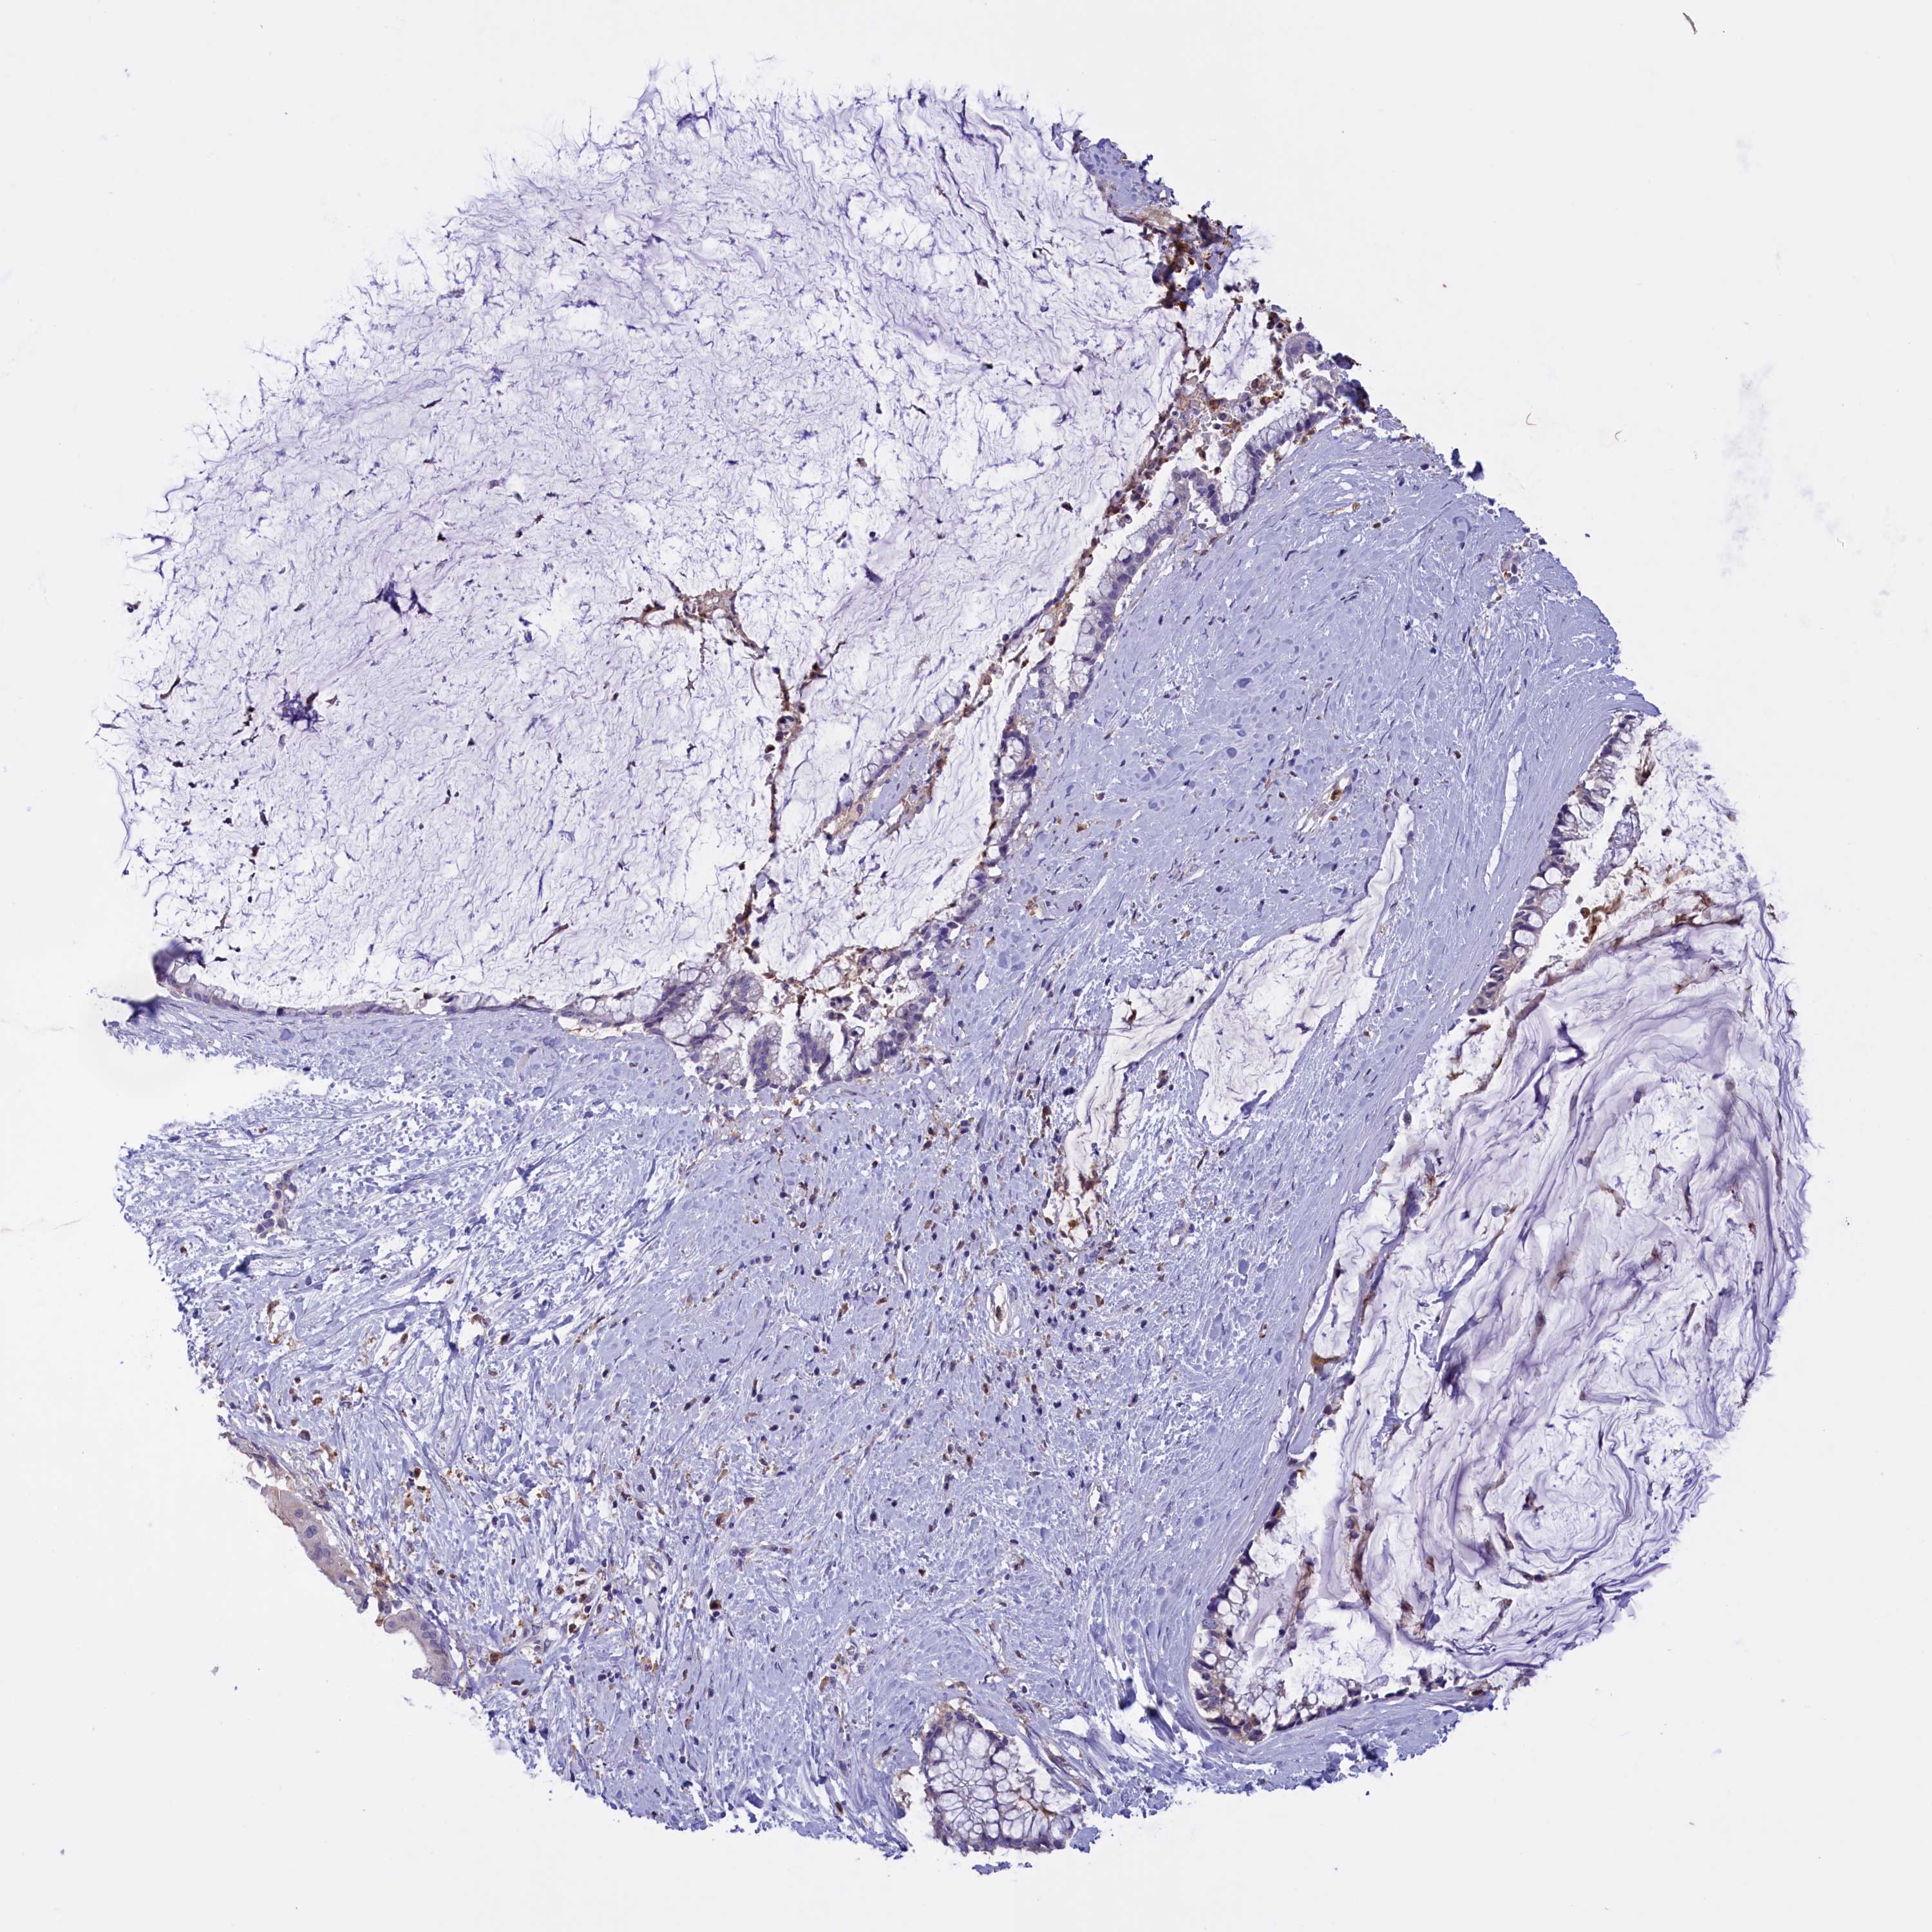

PANCREATIC CANCER - Protein expressioni

A mouse-over function shows sample information and annotation data. Click on an image to view it in a full screen mode. Samples can be filtered based on level of antibody staining by selecting one or several of the following categories: high, medium, low and not detected. The assay and annotation is described here.

Note that samples used for immunohistochemistry by the Human Protein Atlas do not correspond to samples in the TCGA dataset.

Antibody stainingi

Antibody staining in the annotated cell types in the current human tissue is reported as not detected, low, medium, or high, based on conventional immunohistochemistry profiling in selected tissues. This score is based on the combination of the staining intensity and fraction of stained cells.

Each image is clickable and will lead to virtual microscopy that enables deeper exploration of all samples and also displays staining intensity scores, fraction scores and subcellular localization as well as patient and tissue information for each sample.

Antibody HPA039189

Antibody HPA039859

Adenocarcinoma, NOS